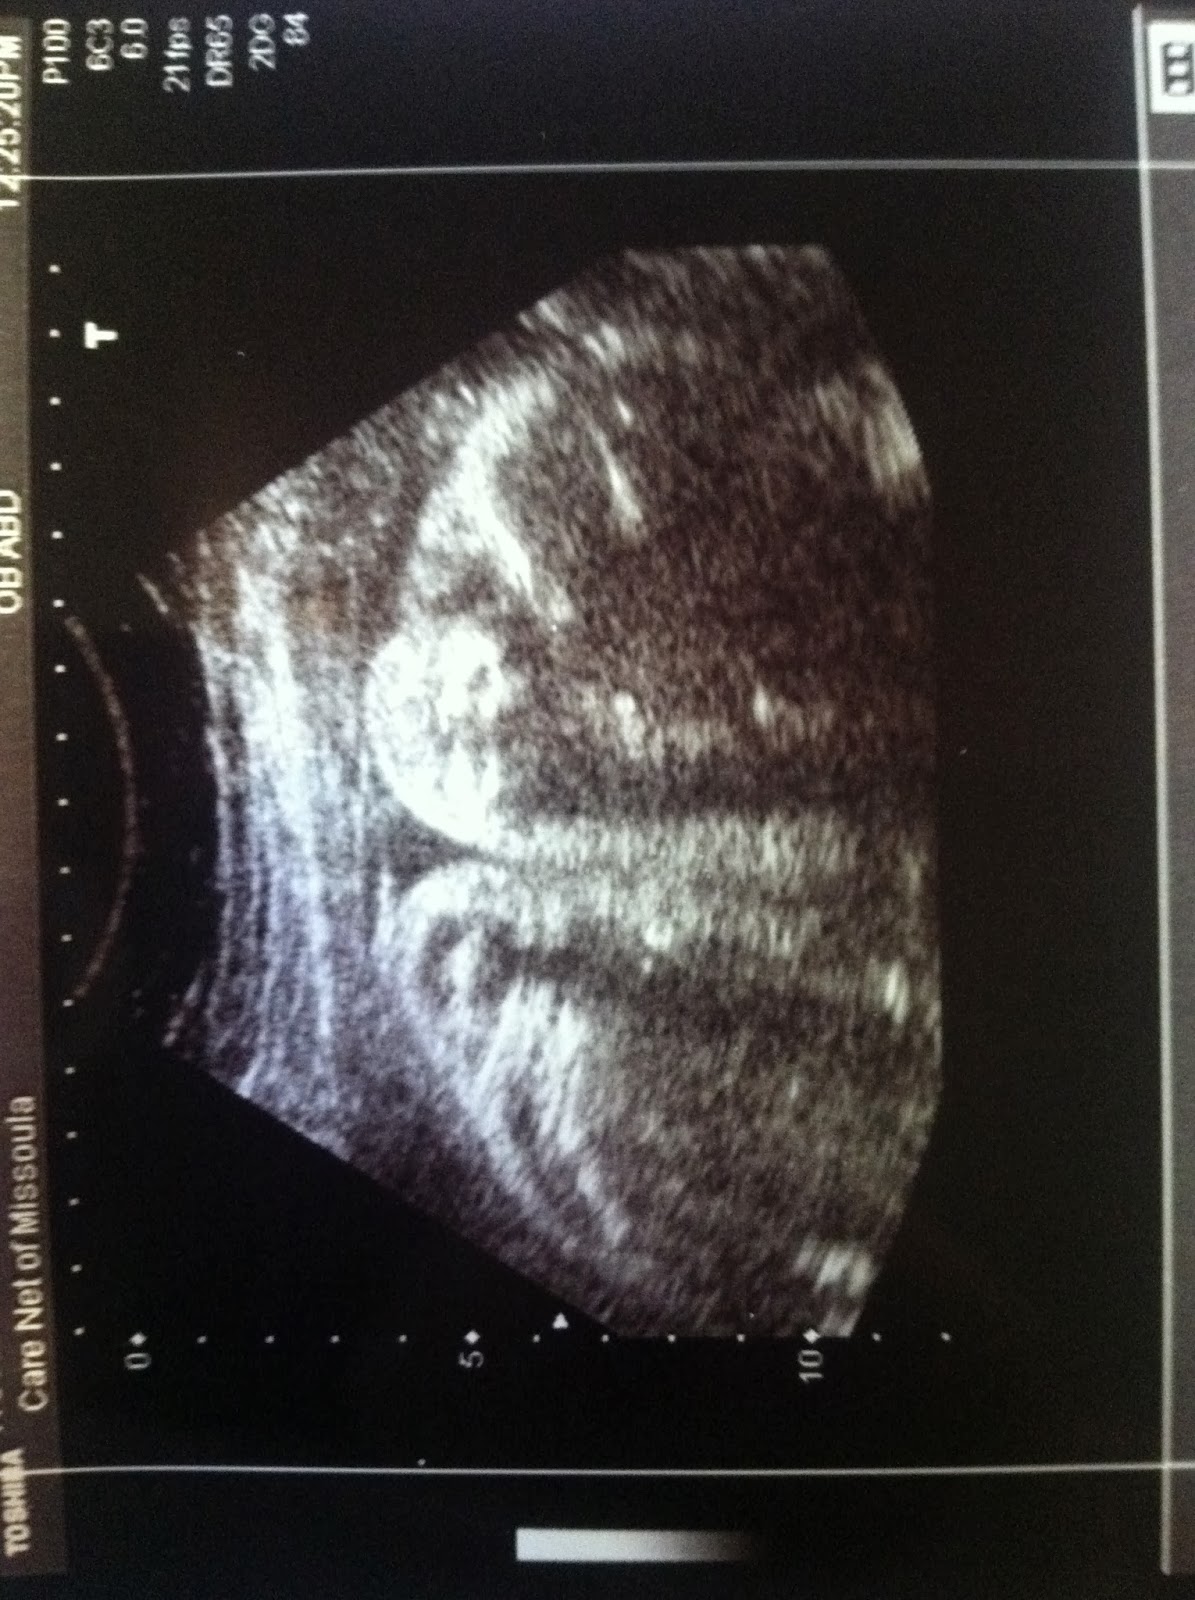

Best moment this week: Having an ultrasound and seeing Little Hocking...let me just say, babies got CHEEKS!

How far along? 31 Weeks

Baby is the size of a: Pineapple

31 Weeks